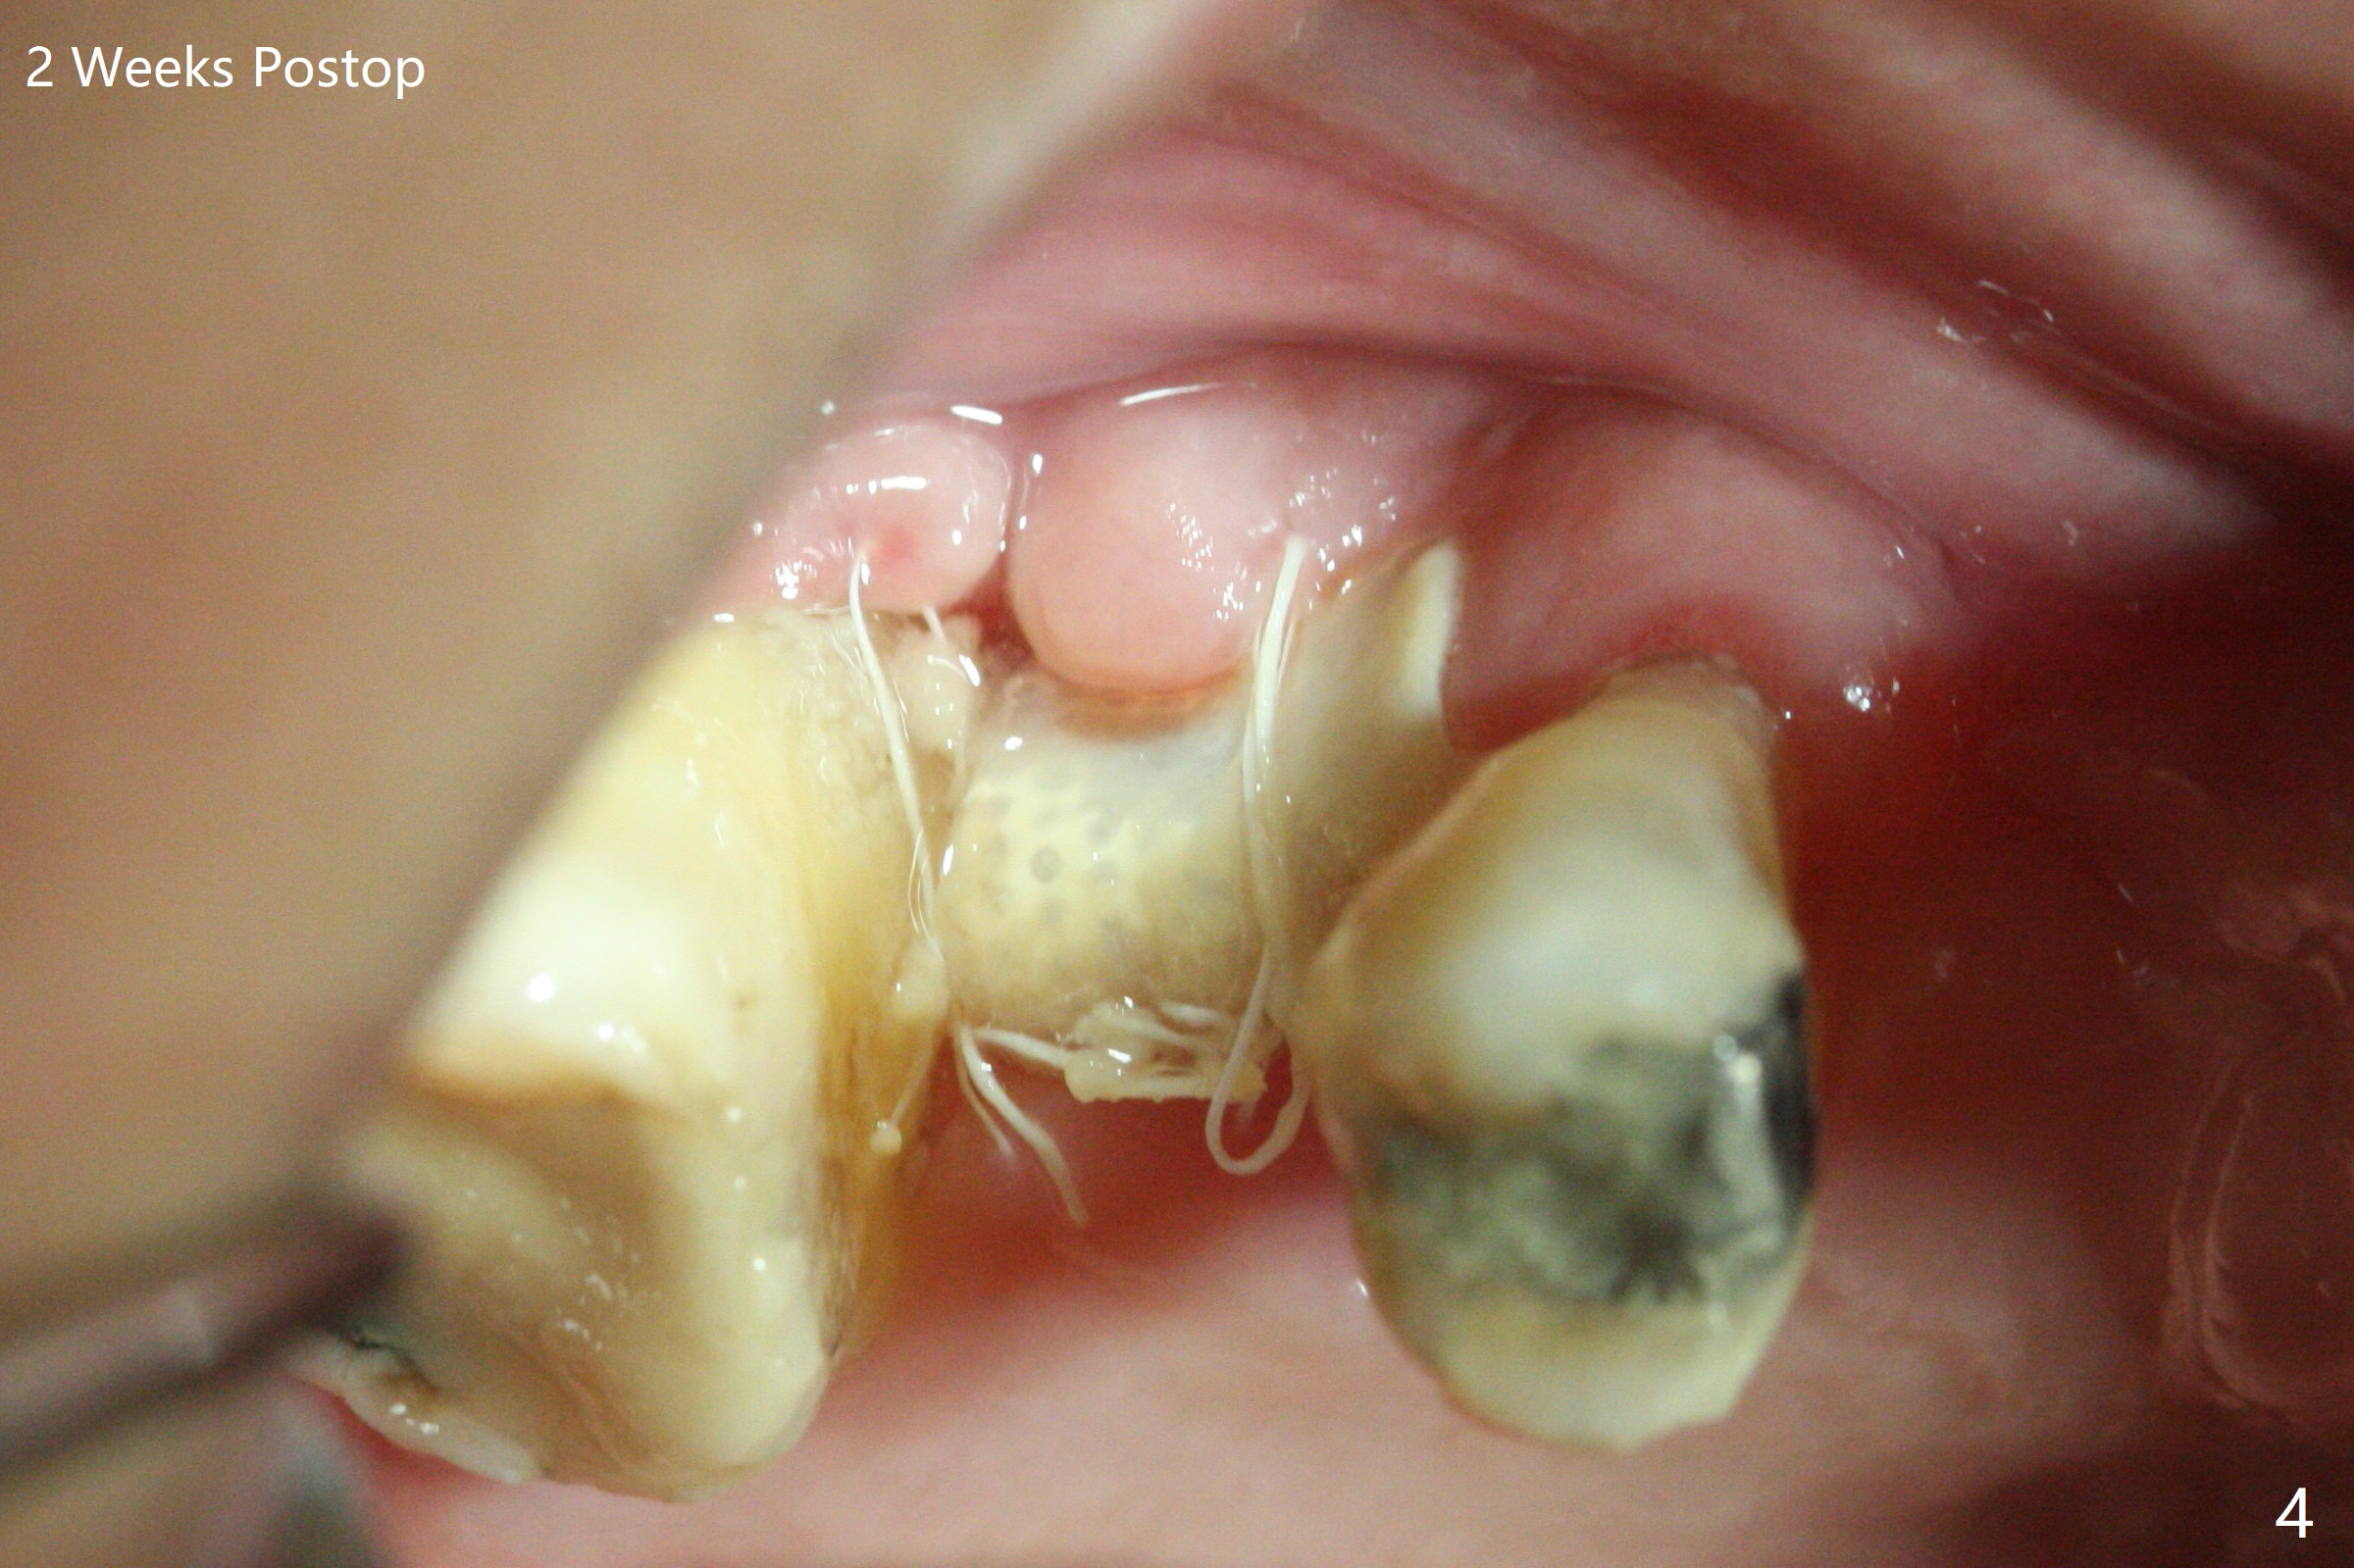

Since the tooth #3 has severe chronic periodontitis with 1 mm sinus floor (Fig.1 *), socket preservation may be not secure (B) in spite of using Cytoplast and PTFE suture. Prior to the bone graft, the sinus floor is lifted easily with Magic Sinus Lifter (IBS America) with Ossogen (mineralized cortical/cancellous (30%/70%) allograft, Fig.1,2 L). Periodontal dressing remains in place because of the neighboring teeth 1 week postop (Fig.3 D). Cytoplast remains in place after dislodgement of the periodontal dressing 2 weeks postop (Fig.4). Cytoplast dislodges 3 weeks postop (Fig.5). Socket preservation is not as secure as immediate implant in term of bone graft retention. What else can be done to prevent bone graft loss?